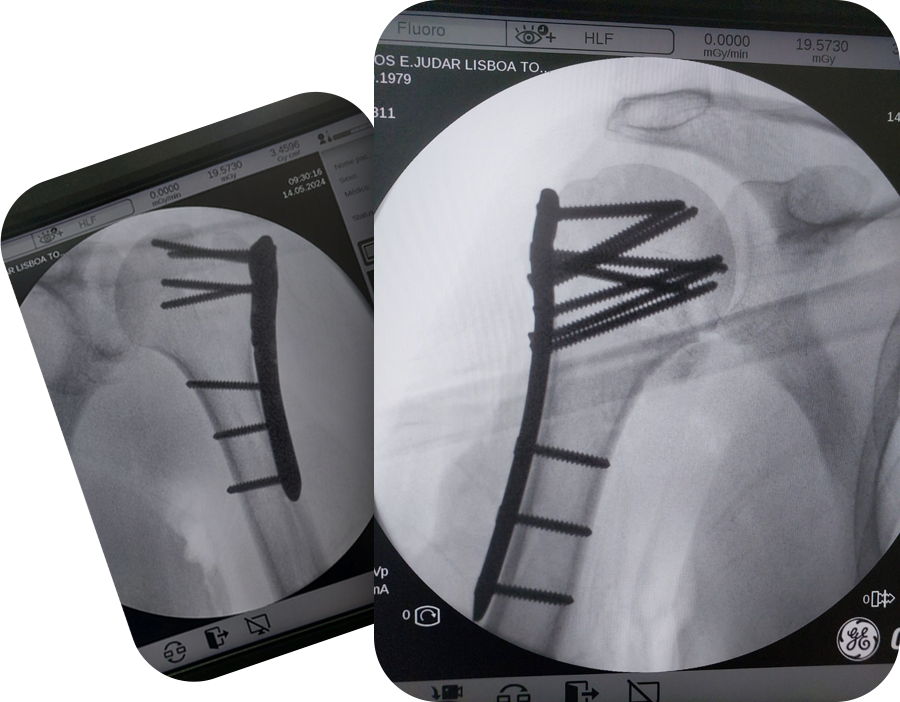

Um Novo Começo: A História do Carlos

No dia 14 de maio, Carlos enfrentou um dos momentos mais difíceis de sua vida. Devido a crises epiléticas, sofreu uma queda grave que resultou na fratura de ambos os ombros e no deslocamento dos braços. O diagnóstico era sério e assustador, mas foi nesse momento que ele encontrou a Dra. Natássia Nava.

Desde o primeiro contato, ela foi clara e transparente. Explicou detalhadamente o procedimento cirúrgico, os pontos positivos e os desafios que ele enfrentaria. Essa honestidade e empatia trouxeram conforto em meio à incerteza. Carlos confiou plenamente nas mãos da Dra. Natássia e seguiu em frente com a cirurgia.

A operação foi um sucesso. Placas e parafusos bilaterais foram necessários, mas o corpo de Carlos respondeu bem, sem infecções ou complicações. Ele relata ter sentido poucas dores no pós-operatório, resultado da combinação entre um trabalho cirúrgico impecável e a adesão rigorosa às orientações médicas.